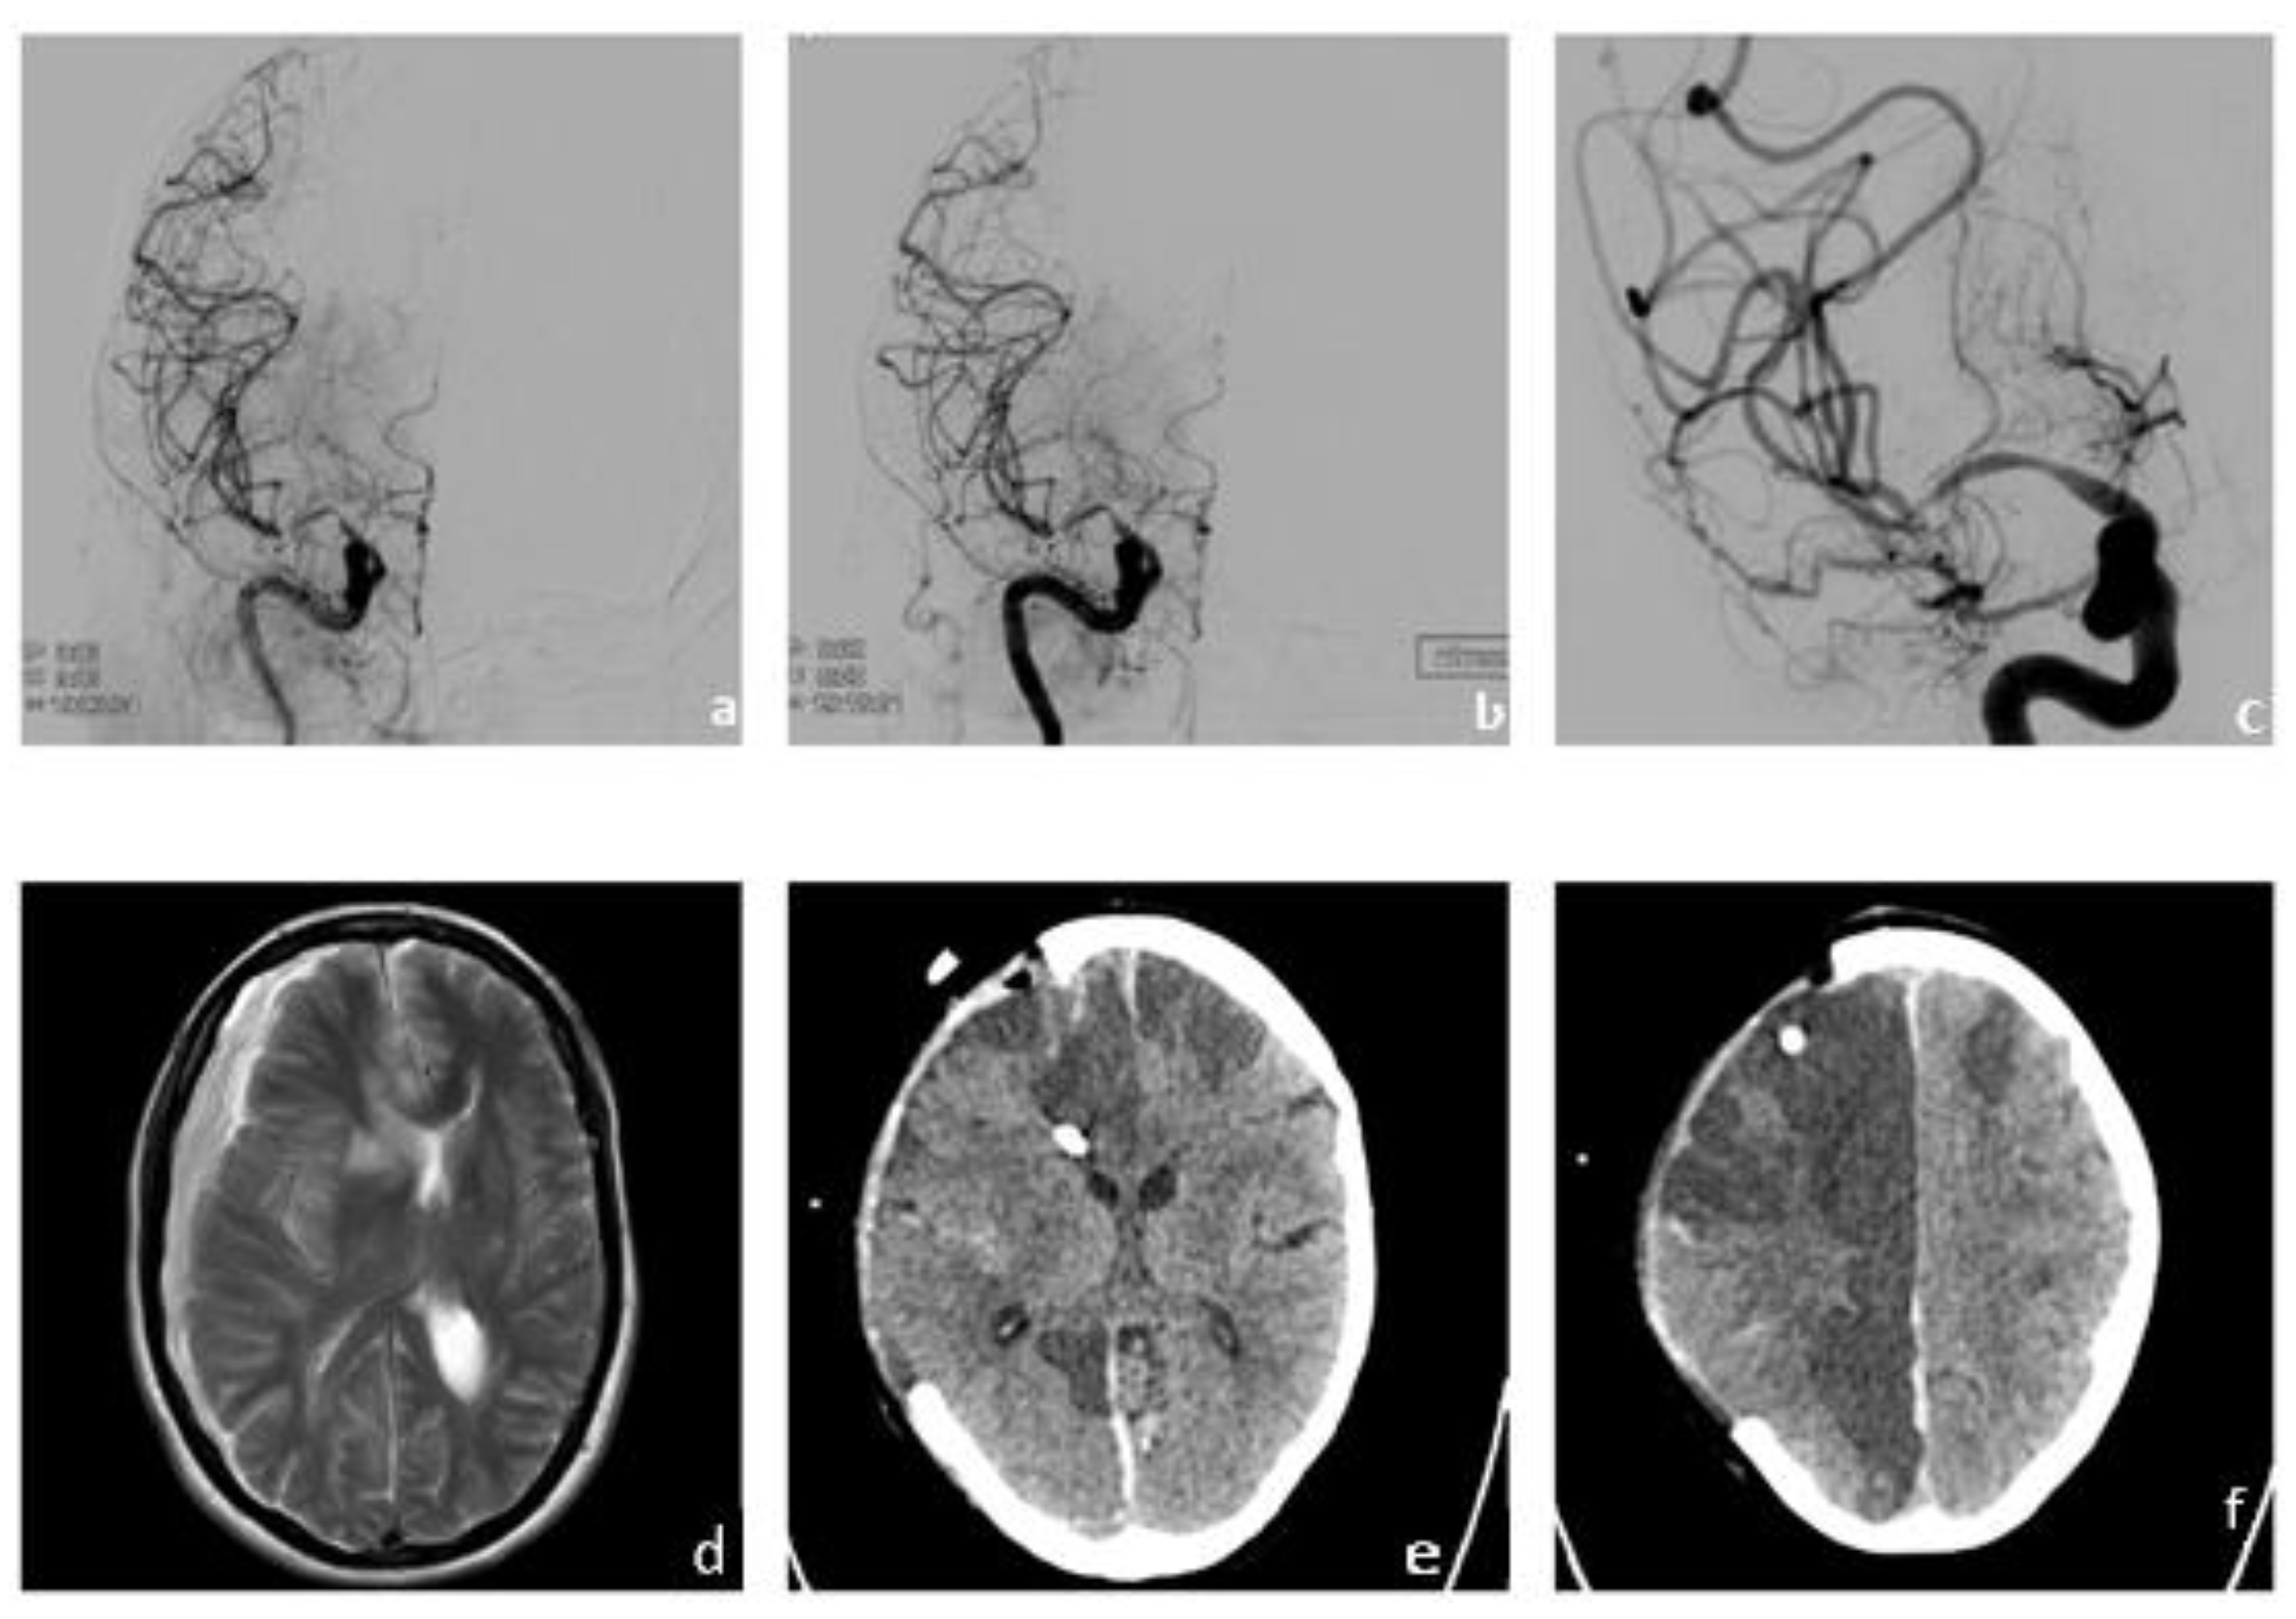

On the second day after admission, the patient showed severe neurological deterioration with new onset of left-sided hemiparesis, gaze paresis to the left, and tactile neglect (NIHSS 9). Diagnostic cerebral computed tomography showed stenoses of the right MCA and ACA and extensive perfusion deficits next to already demarked infarction in the territory of the right ACA, as previously diagnosed on initial cMRI (Figure 2a–c). An emergency angiography confirmed the hemodynamically relevant stenoses of the right MCA and ACA. Perfusion and stenosis was improved by interdisciplinary consented vasospasmolysis with nimodipine and a percutaneous transluminal angioplasty (PTA) of the right MCA with a remodeling balloon. The proximal stenosis of the MCA was relatively rigid and did not behave as, e.g., vasospasm, due to subarachnoid hemorrhage. The intervention (Figure 2d–e) resulted in almost complete remission of the aforementioned neurological symptoms until day [11], when the patient showed recurrent episodes of initially milder neurological symptoms (e.g., reduced coordination of the left hand) that were repeatedly successfully treated with vasospasmolysis and best medical treatment (altogether seven interventions, Figure 2f). On day 19, however, the neurological symptoms worsened again with severe hemiparesis of the left side and neglect. A multimodal CT showed further worsening of the stenoses and severely reduced cerebral perfusion in the right MCA territory. In interdisciplinary consensus, we performed another PTA of the two high-grade stenoses in the proximal M1 and distal M1 segments of the right MCA after application of 3000 IE heparine. Intraprocedural re-stenosis after PTA necessitated stenting. After administration of 500 mg acetylic salicylic acid (ASA) and initiating an eptifibatide therapy (bolus followed by permanent infusion, body weight adapted) we implanted a self-expanding, fibrin–heparin-coated nitinol microstent (CREDO heal, 4 × 15mm, Acandis, Pforzheim, Germany) in the proximal M1 segment of the right MCA (Figure 3a–c). The perfusion of the right MCA was significantly improved (Figure 3c); angiograms and a flat panel CT showed no complications.

Figure 2. Progressive deterioration of cerebral perfusion due to vascular stenosis and vasospasms caused by vasculitis. Progressive right frontal infarct demarcation (a) and new onset of stenosis and vasospasms (b) leading to massive bihemispheric perfusion delays (c). Endovascular vasospasmolysis (d) and PTA of high-grade stenoses of the MCA (e) shows significant reduction of the aforementioned perfusion delays (f).